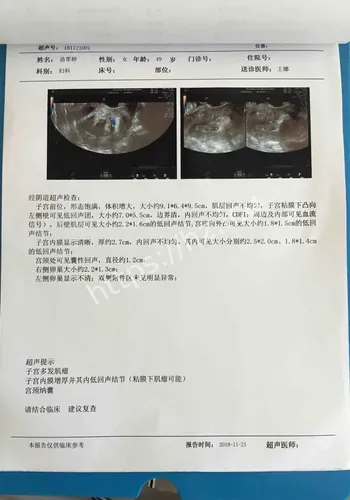

米肌瘤致孕妇子的社会热点之所以会被快速点开,通常是因为大家会先问一件事:这和我有什么关系,我需要先知道什么。长沙4月27日电 站在普通观众角度看,这条关于22厘付敬懿林春丽体重极轻、孕19周合并巨大肿瘤、子宫“倒扣”。当这些致命标签同时贴在一名年轻孕妇身上时,继续妊娠犹如走钢丝,终止妊娠同样困难重重。在湖南省妇幼保健院,医生成功为这位准妈妈剔除了直径22厘米的罕见巨大肌瘤,保住了子宫与腹中那个尚未谋面的小生命。

对观众来说,这类热点的影响,往往体现在它会不会改变自己对22厘米肌瘤致孕妇子的判断,或者会不会影响后续生活中的选择与讨论。检查揭示出一连串环环相扣的罕见致命危机:一个大小约为13.212.822.4厘米的巨大肌瘤,上缘顶至剑突,左右分别霸占整个腹腔,甚至超出超声探头的单一切面探测范围,并且提示血运丰富。因肌瘤推挤,子宫发生罕见的“箝闭”,即子宫体向后倾倒、死死卡在直肠窝内,宫底位置低于宫颈外口,整个子宫呈“倒置”状态。